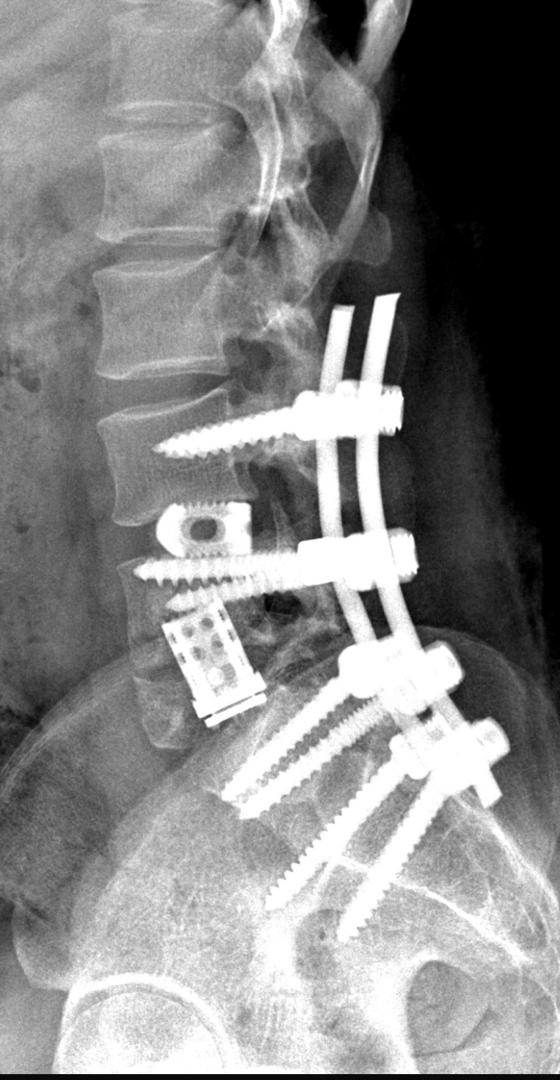

Spines